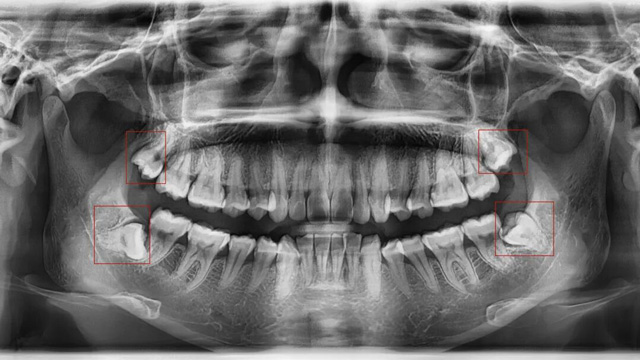

01智齿挤压邻牙,导致牙齿拥挤/移位

这是最常见的拔除原因。正畸的核心需求之一一般是“排齐拥挤牙齿”,而智齿作为口腔中最后萌出的牙齿(通常在20岁左右萌出),由于生长位置特殊、空间有限,很可能会持续挤压旁边的第二磨牙,导致第二磨牙倾斜、移位,进而引发整个牙列拥挤。

如果不拔除这颗“肇事智齿”,即使通过正畸排齐了牙齿,后期也会因为智齿的持续挤压,导致牙齿再次拥挤、反弹。

如果通过X光片发现,你的智齿已经顶到邻牙牙根,或者导致邻牙出现龋坏、牙周炎,无论是否正畸,都建议尽早拔除。